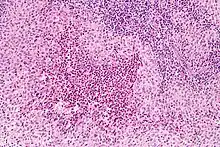

| Micrograph showing a Langerhans cell histiocytosis with the characteristic reniform Langerhans cells accompanied by abundant eosinophils. H&E stain. | |

Diagnosis is confirmed histologically by tissue biopsy. Hematoxylin-eosin stain of biopsy slide will show features of Langerhans Cell e.g. distinct cell margin, pink granular cytoplasm.[33] Presence of Birbeck granules on electron microscopy and immuno-cytochemical features e. g. CD1 positivity are more specific. Initially routine blood tests e.g. full blood count, liver function test, U&Es, bone profile are done to determine disease extent and rule out other causes.[34]